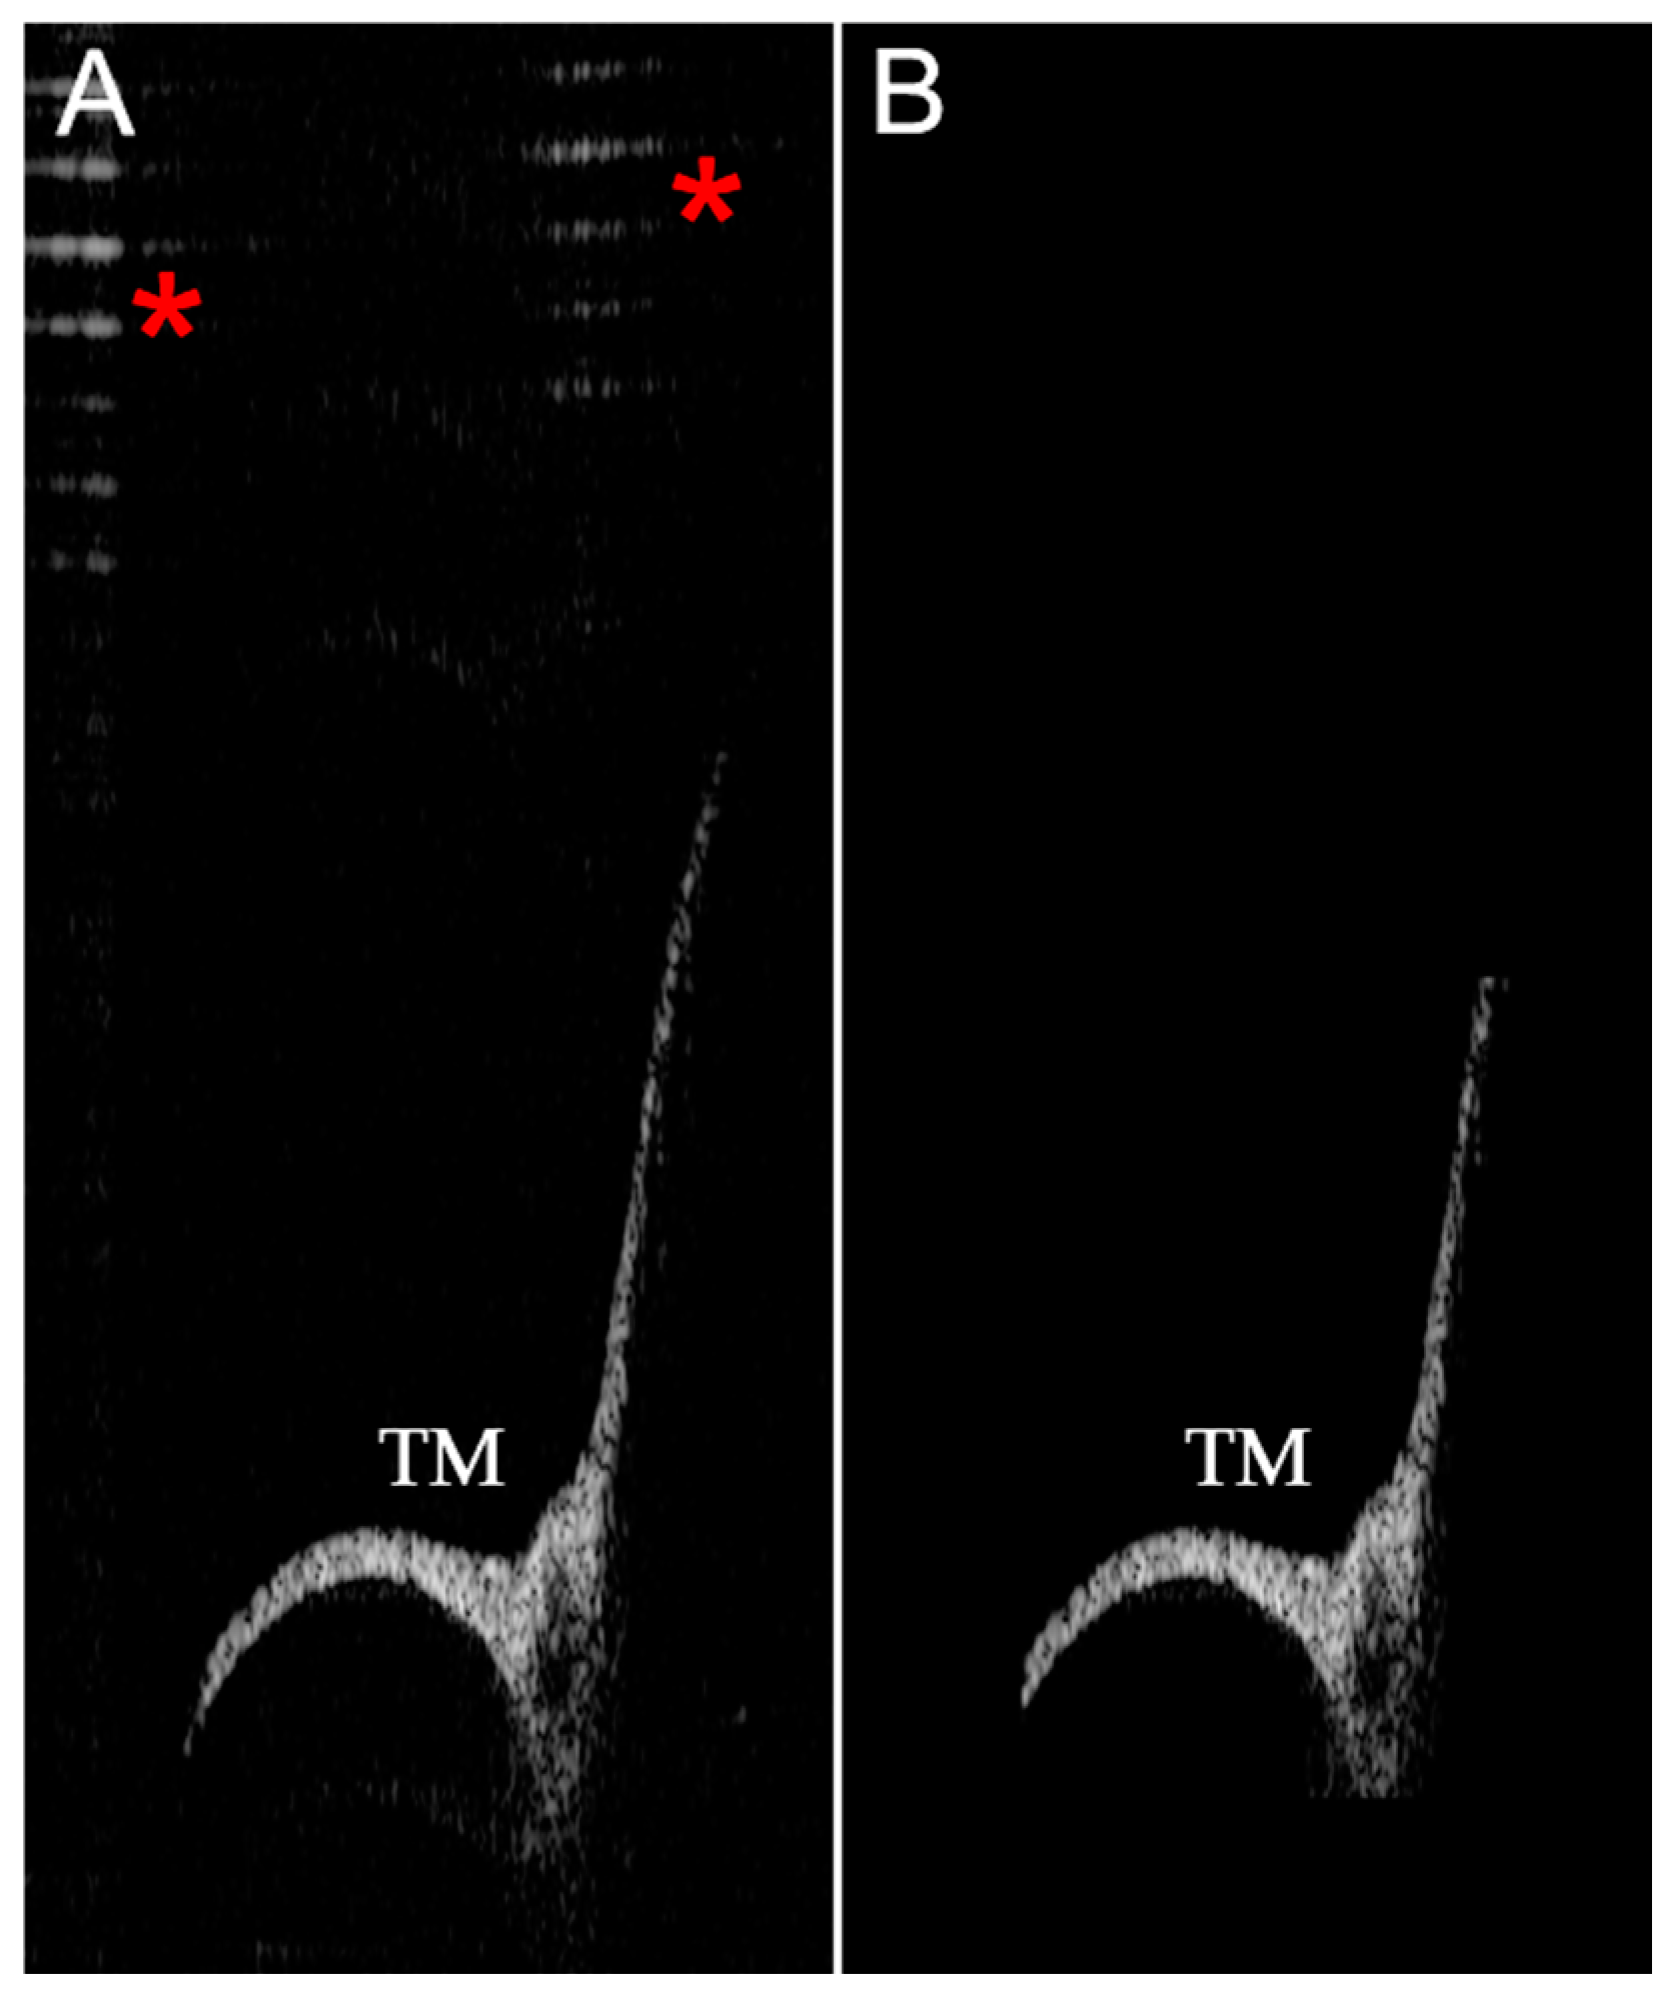

2.5. Image Recognition Algorithms

2.6. 3D Reconstruction Algorithm

3. Results